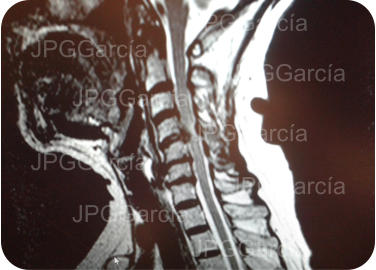

Estudio de control postquirúrgico inmediato

Estudios de control postquirúrgico radiográfico y de resonancia magnética